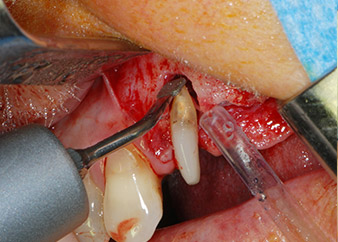

Un mese più tardi, nel giorno programmato per l'intervento, il dolore e l'infiammazione in corrispondenza del dente 24 erano minimi, ma era ancora presente mobilità di classe 2 secondo Miller. Dopo l'apertura dei lembi e la pulizia del tessuto periapicale e periradicolare infetto, l'estensione della mancanza ossea si è resa evidente (Figg. 2 e 3).

Tutto il tessuto osseo vestibolare e distale era mancante in corrispondenza della radice buccale. La possibilità di attacco era essenzialmente ristretta alla radice palatale, evidenziando la prognosi negativa preliminare. Anche il dente 27 mostrava un punto di attacco orizzontale ridotto e una rarefazione apicale minima (cfr. Fig. 1), senza sintomi clinici.

perdita totale di tessuto osseo e attacco

Fig. 2 e 3: Dopo aver sollevato i lembi, un mese dopo il pretrattamento endodontico e l'inizio della terapia periodontale sull'intera dentatura, la radice buccale del dente 24 mostrava una perdita totale di tessuto osseo e di punti di attacco.